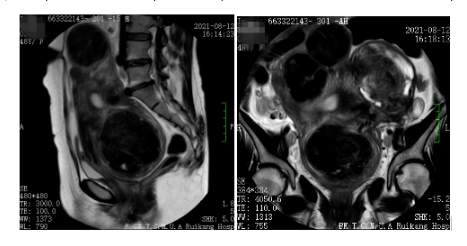

2021年8月12日:盆腔MR平扫+增强:子宫体积明显增大不规则,子宫肌壁见多发类圆形异常信号影,部分向外突出,边界清晰,呈等T1短T2信号,信号不均,较大一个病变大小约81mmx99mmx85mm,不均匀强化。考虑子宫多发肌瘤。